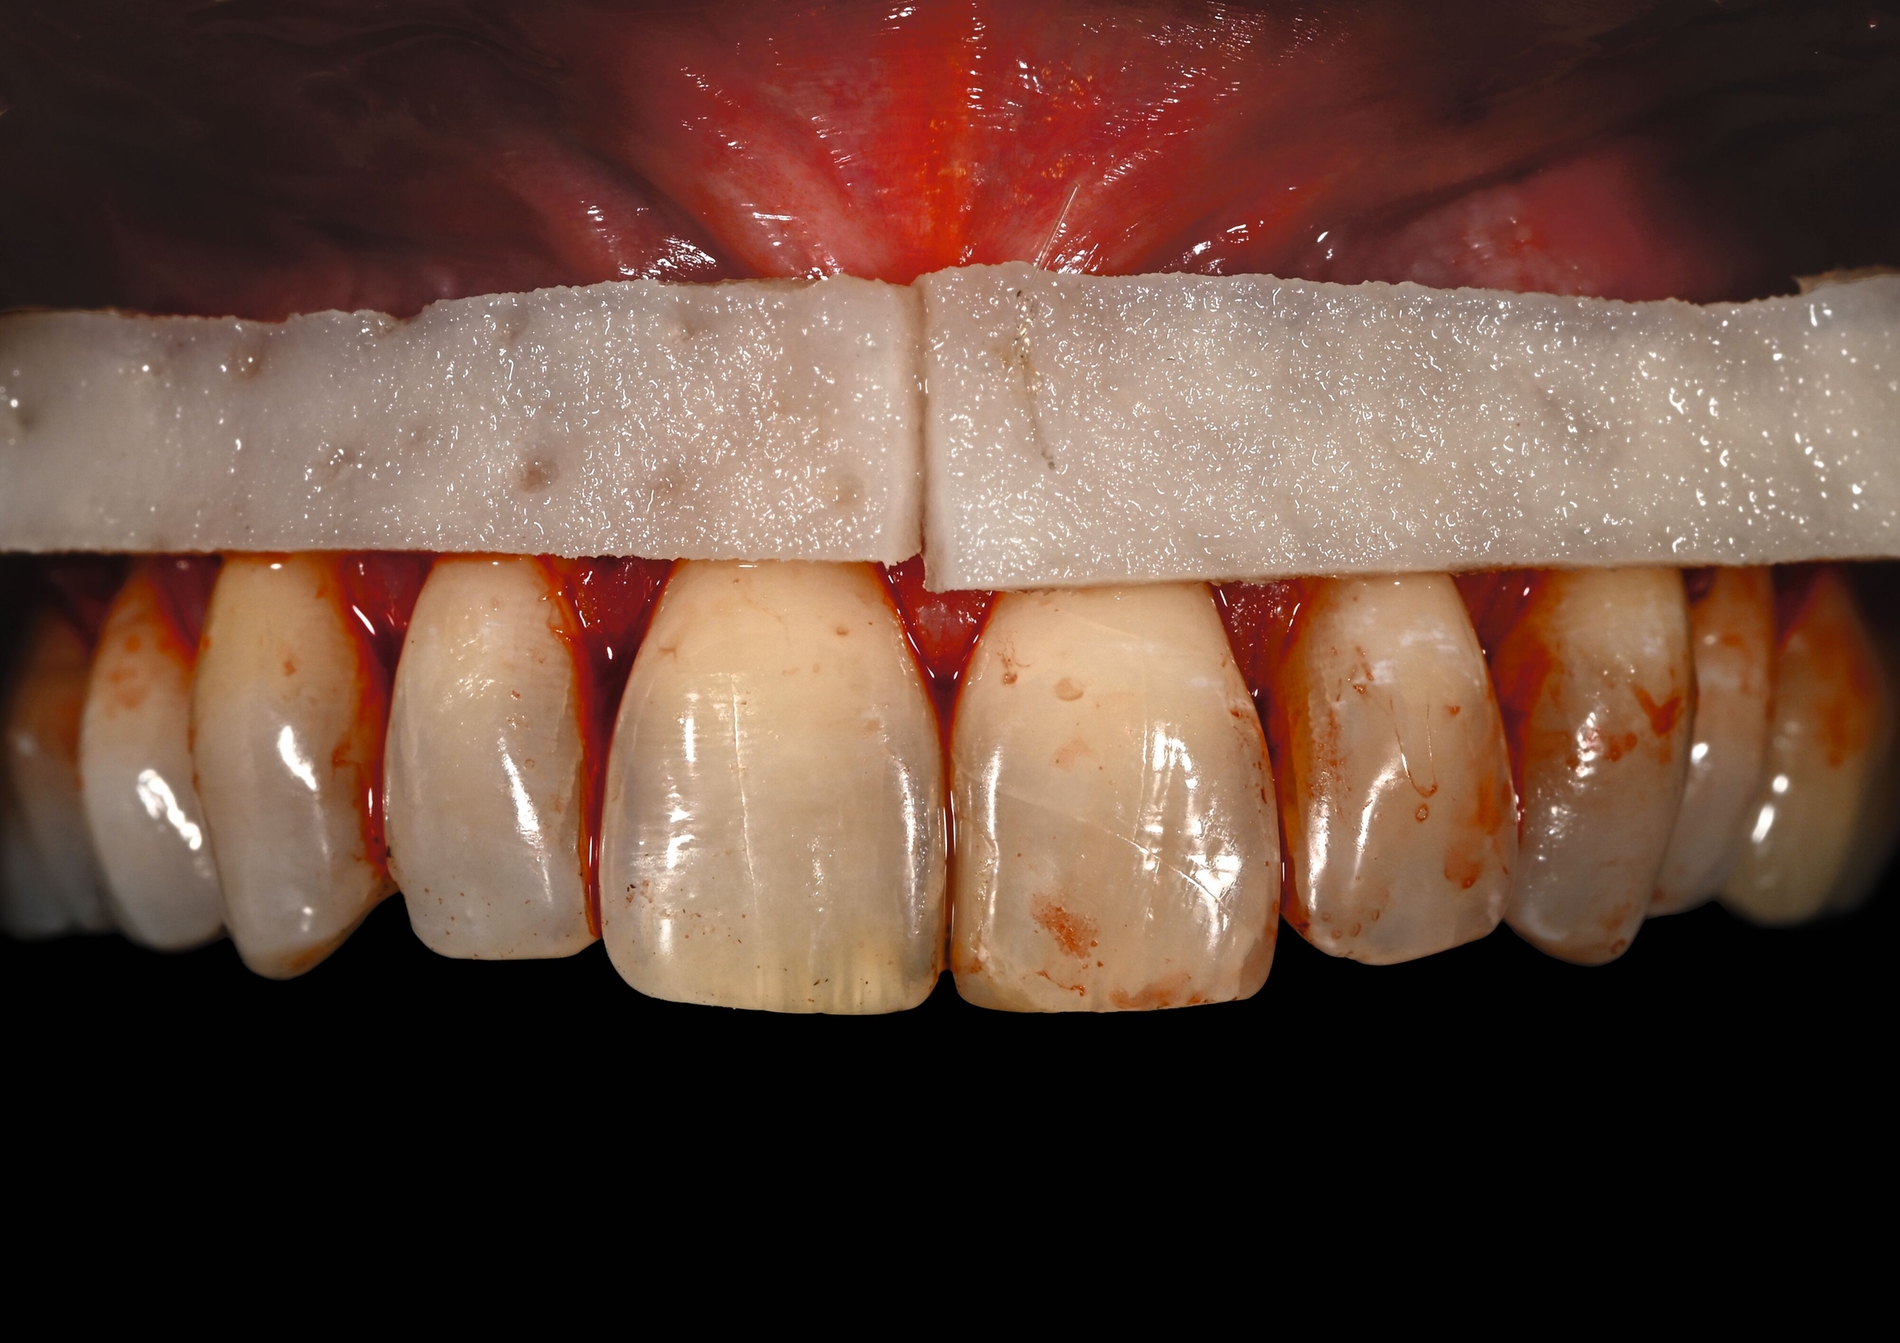

Trotz des Verbleibs des Epithels kann es zu sekundärer Wundheilung mit entsprechender Morbidität postoperativ kommen, besonders bei Techniken, die mehrere Inzisionen beinhalten, wie den sogenannten Trap-Door-Techniken, so dass sich die „Single-Incision-Technik“ durchgesetzt hat [Fickl et al., 2014]. Gegen eine übermäßige Blutung und postoperative Morbidität empfiehlt sich klinisch die routinemäßige Anwendung einer Verbandplatte, entweder in der Tiefziehtechnik oder präoperativ mittels eines Thermoplasts, so dass sich früh ein stabiles Blutkoagel bildet und die Wundheilung an der Entnahmestelle ungestört ablaufen kann. Dadurch wird die Morbidität klinisch deutlich reduziert. Das sBGT zeigt ästhetisch sehr gute Ergebnisse mit Blick auf Oberflächenstruktur sowie Farbe und kann unter anderem im Rahmen der Envelope- oder Tunneltechnik oder auch über einer Extraktionsalveole bewusst exponiert belassen werden, um zusätzlich befestigte Gingiva zu gewinnen.

Die Wundheilung nach dieser Technik erfolgt anders als beim sBGT immer sekundär, somit wurden bei Vergleichsstudien eine signifikant erhöhte Morbidität, Schwellungen und ein erhöhtes Nachblutungsrisiko beschrieben [Del Pizzo et al., 2002; Griffin et al., 2006], was jedoch bei entsprechender Versorgung des Gaumens umgegangen werden kann [Zucchelli et al., 2010]. Die Versorgung der Spenderregion kann mit Kollagenvlies, Cyanoacrylatkleber, Verbandplatte oder einer Kombination erfolgen. Dies kann die Morbidität deutlich reduzieren [Tavelli et al., 2019b]. Ein Vorteil von dBGT ist die Stabilität der Gewebedicke im Laufe der Zeit, was im Gegensatz zur beschriebenen Schrumpfung von sBGT steht, die häufig beobachtet wird [Zucchelli et al., 2018].